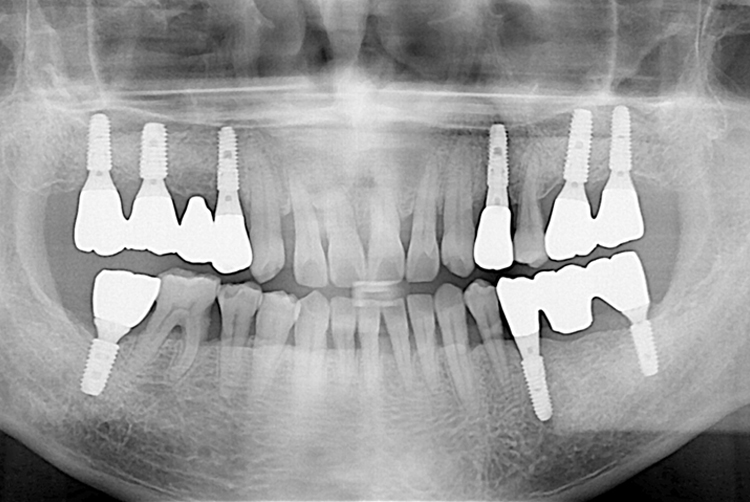

치료후 : 2019-12-13

세종치과는 많은 환자와 다양한 케이스를 바탕으로 항상 편안한 임플란트 수술을 제공하고자 노력하고,

오래동안 튼튼히 쓸 수 있는 임플란트 수술을 가장 큰 목표로 삼고 있습니다